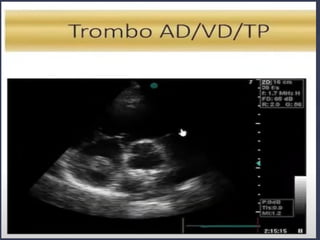

● Este paciente tem SCA, IC, TEP, Tamponamento,

Dissecção???

SIM, NÃO e INCONCLUSIVO